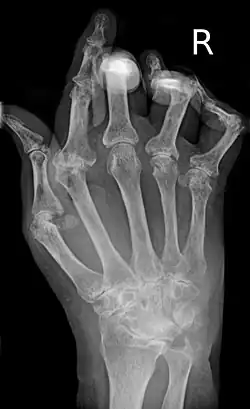

| A hand severely affected by rheumatoid arthritis. This degree of swelling and deformation does not typically occur with current treatment. | |

As the pathology progresses, the inflammatory activity leads to tendon tethering and erosion and destruction of the joint surface, which impairs range of movement and leads to deformity. The fingers may develop almost any deformity depending on which joints are most involved. Specific deformities, which also occur in osteoarthritis, include ulnar deviation, boutonniere deformity (also "buttonhole deformity", flexion of proximal interphalangeal joint and extension of distal interphalangeal joint of the hand), swan neck deformity (hyperextension at proximal interphalangeal joint and flexion at distal interphalangeal joint) and "Z-thumb." "Z-thumb" or "Z-deformity" consists of hyperextension of the interphalangeal joint, fixed flexion, and subluxation of the metacarpophalangeal joint and gives a "Z" appearance to the thumb.[16]: 1098 The hammer toe deformity may be seen. In the worst case, joints are known as arthritis mutilans due to the mutilating nature of the deformities.[20]

X-rays of the hands and feet are generally performed when many joints are affected. In RA, there may be no changes in the early stages of the disease, or the X-ray may show osteopenia near the joint, soft tissue swelling, and a smaller than normal joint space. As the disease advances, there may be bony erosions and subluxation. Other medical imaging techniques such as magnetic resonance imaging (MRI) and ultrasound are also used in RA.[20][79]